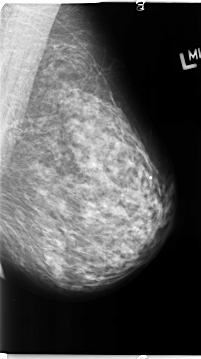

B_3133_1.RIGHT_MLO

RIGHT_MLO LINES 4624 PIXELS_PER_LINE 2752 BITS_PER_PIXEL 12 RESOLUTION 50 OVERLAY